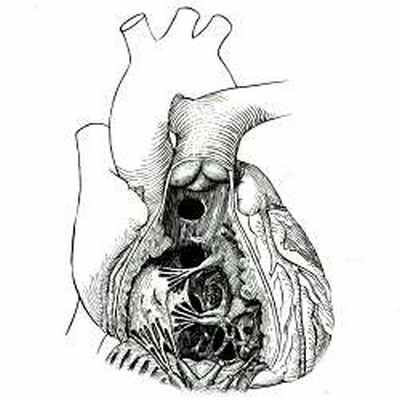

Дефекты межжелудочковой перегородки могут располагаться в ее мембранозной или мышечной части (рис. 10), а в ряде случаев имеется полное отсутствие перегородки между желудочками.

![]() | Рис. 10 Схема локализации основных типов дефектов межжелудочковой перегородки: (сверху вниз) надгребешковый, подгребешковый, канальный, мышечный типы. |